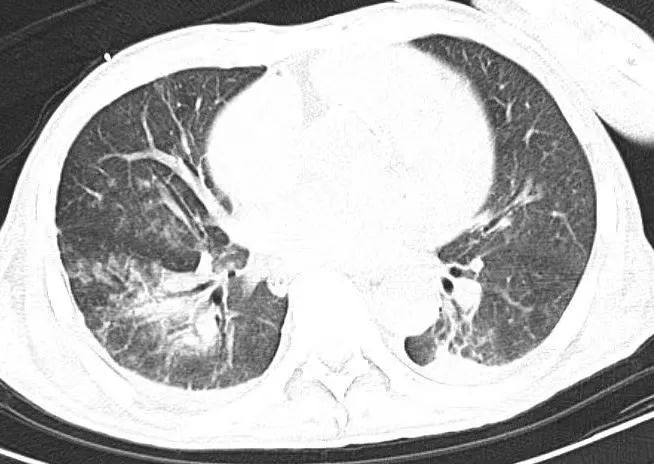

(第二次胸部CT)

第四天,患者呼吸指标基本正常,经认真评估,患者顺利撤除呼吸机,继续进行抗感染、抗心衰对症用药,严密监测各项生命指征。蒋主任每日带领医护团队在患者床旁交接班,及时调整诊疗方案,想方设法为患者排忧解难,帮助他共渡难关。再次复查胸部CT,影像显示明显好转。重症医学科的医护们由衷地感到高兴,越发有了干劲。